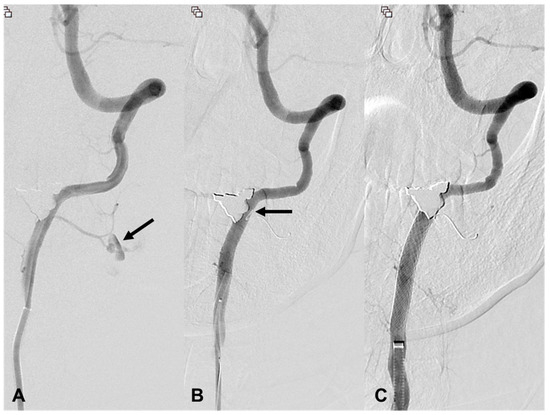

| 6 | 51/F | TA | Epistaxis and oral bleeding | Le fort I fracture | EV, R petrous ICA EV, R ascending pharyngeal | cStent, coil | Stable 423 d F/U |

| 15 | 34/F | Stab | Bleeding | EV, R ICA | EV, R cervical ICA | cStent | Stable 45 d F/U |